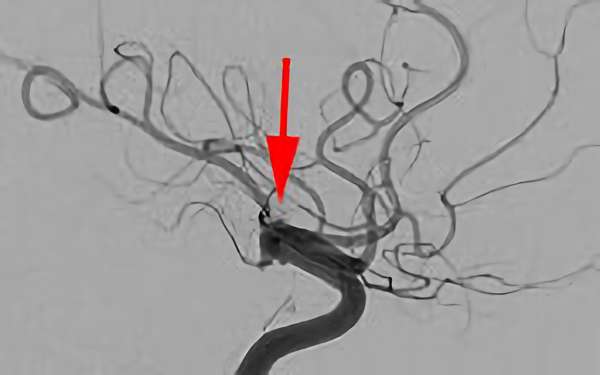

前交通動脈瘤

No.1627 手術後